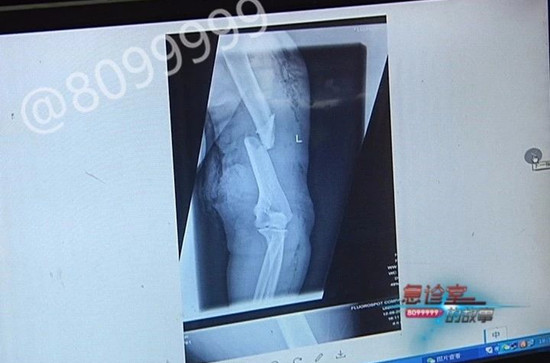

由于邓阿姨受伤后两天才从文山送到昆明,检查结果为肱骨开放性粉碎性骨折,肱动脉也有损伤,缺血时间和伤口暴露时间也很长,因此手术过程极具危险性。

云南骨科医院修复重建显微外科 主任 陈祥春介绍道,受伤到现在已经好多天了,伤者的血管也不够长,我们需要做血管移植,操作技术并不难,难的是这个特殊因素,因为拖的时间太长了,她的前臂肌肉大片是坏死的话,恐怕这个胳膊也保不住。